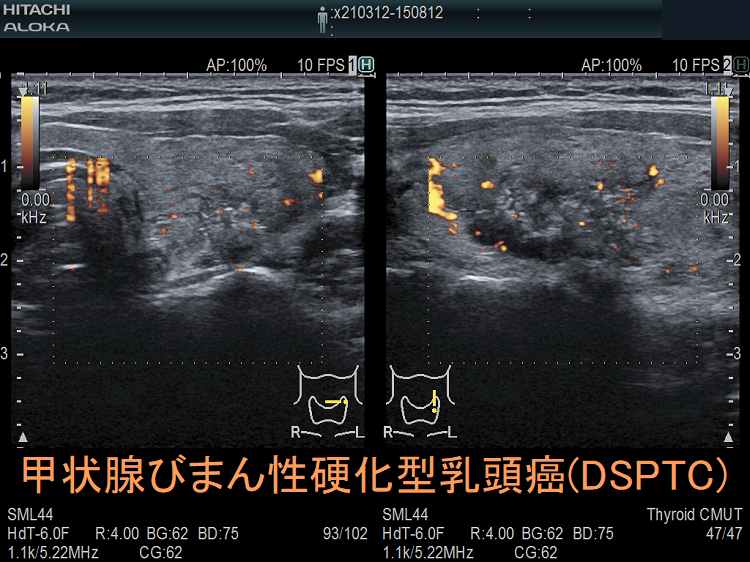

- 甲状腺超音波(エコー)検査において、不均一な病変で

等エコー(48.4%)、びまん性粒状石灰化(52.3%)、血流は乏しい(71.6%)

- 甲状腺エコーで、境界不明瞭で不均質な病変;等エコー(48.4%)、びまん性粒状石灰化(52.3%)、血流は乏しい(71.6%)[Clin Radiol. 2022 May;77(5):e356-e362.]

(エコー画像;Ultrasonography. 2017 Apr 36(2) 103–110.)